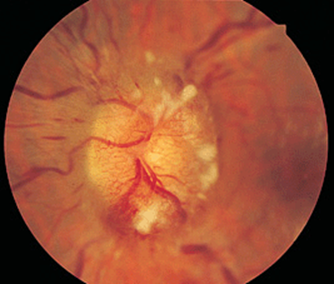

FIGURE 21-12

Papilledema means optic disc edema from raised intracranial pressure. This obese young woman with pseudotumor cerebri was misdiagnosed as a migraineur until fundus examination was performed, showing optic disc elevation, hemorrhages, and cotton-wool spots.